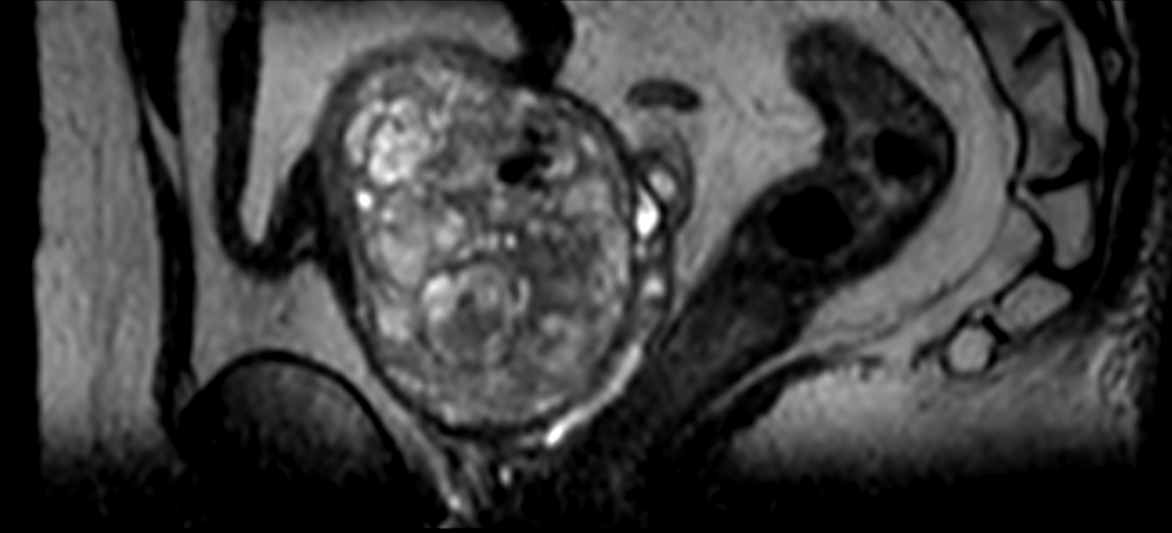

4D FreeBreathing (subtraction)

-